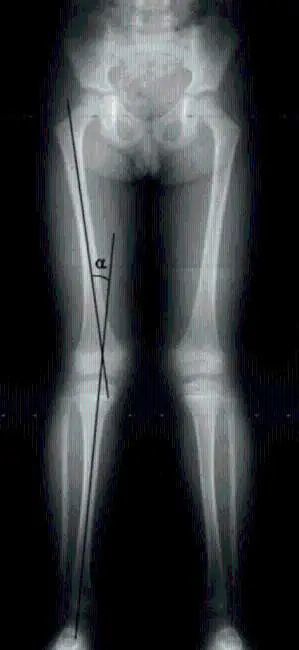

“X型腿”其实是一种状态,我们肉眼直观看过去的状态:双腿站立是呈X型。

膝外翻才是X型腿真正的医学上的名称。站立时,双膝并拢,脚踝没有办法并在一起,就是膝外翻。